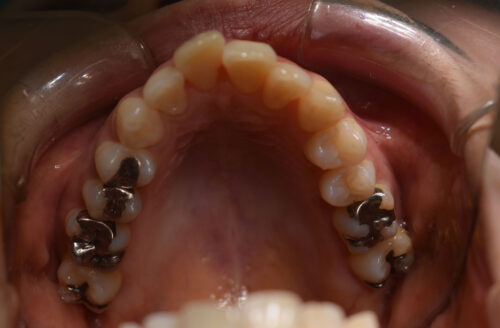

初診時年齢 39歳 女性

歯のでこぼこ(叢生)

を主訴に

池袋よりひとつ隣駅の東京都豊島区大塚駅すぐの大塚たまみ矯正歯科へ

いらっしゃいました。

奥歯のかみ合わせに 前後的な ずれは ないものの

上下ともに 前歯部に

顕著な 叢生(でこぼこ)が

認められました。